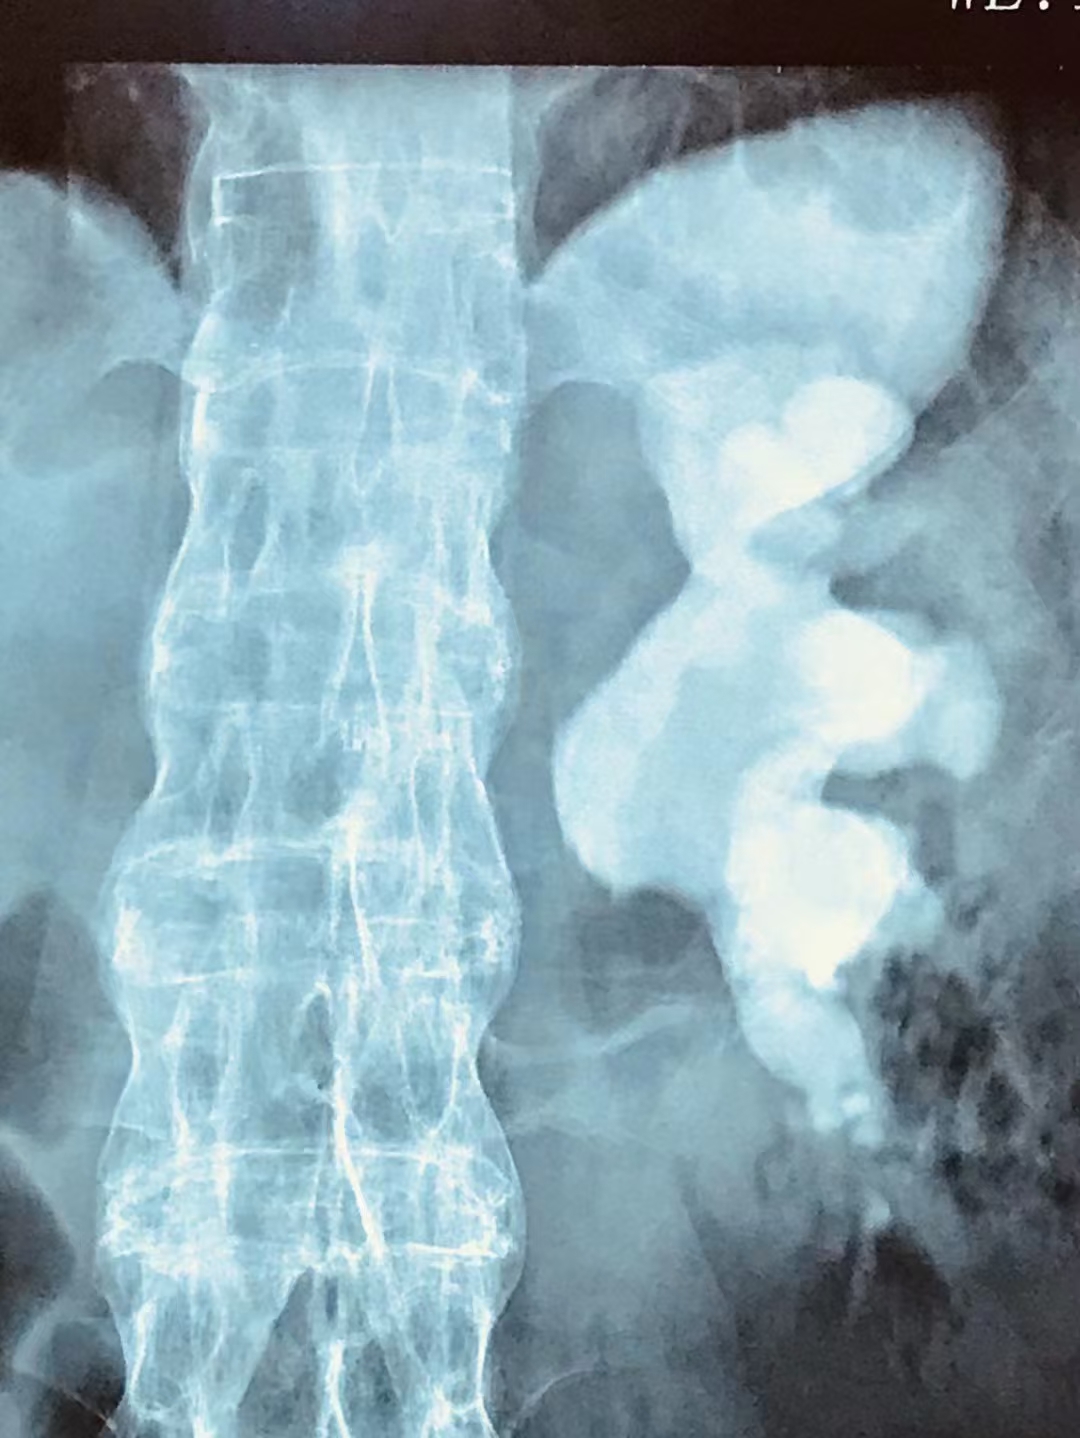

很多人都认为肾结石没有感觉到疼痛就不要紧、不用采取治疗,这种认识是错误的。拖延治疗很可能会使病情不断地加重,进而导致非常严重的后果。肾脏长了结石相当于存在异物,如果这种异物长期存在于肾脏里面,持续地摩擦、刺激肾脏,可能会引起肾脏反复感染、肾周围炎、肾周围脓肿、肾积脓等。

图片来源自网络,侵权请联系删除

结石还有可能会导致泌尿系统的梗阻,从而引起肾积水,可导致肾功能损伤、肾萎缩,严重的会出现肾功能衰竭,俗称尿毒症。因此,肾结石不管有没有症状,都应早发现早治疗。